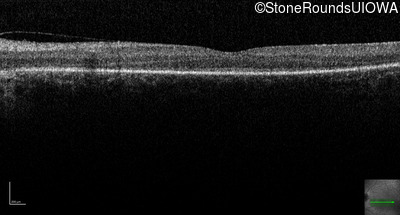

Age at visit:

28 years

OD

OS

Light Perception

OCT Stack

SECORD

RPGRIP1

His631Arg CAC>CGC

Pro237 del1ccA

AR